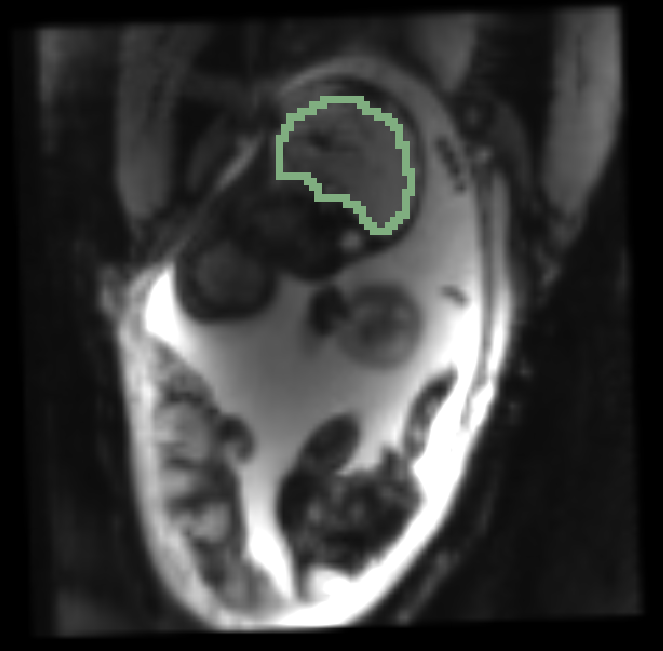

, manual segmentation on , manual segmentation on , propagated segmentation

, manual segmentation on , manual segmentation on , manual segmentation on

Fig. 3 provides example results from the study for fetal brains and placentae. We observe that the reference frame is warped accurately by the temporal registration algorithm in the regions of fetal brains and placentae to represent the first frame in the series that is substantially different from the template. The delineations achieved by transferring manual segmentation labels from the reference frame to the coordinate system of the selected frame are in good alignment with the manual segmentation outlines for that selected frame.